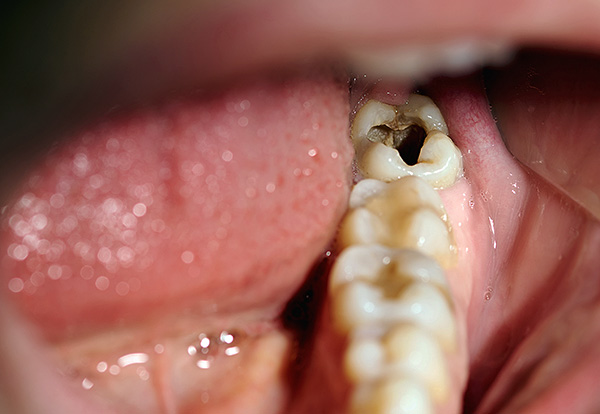

A foto abaixo mostra a cárie média localizada na região da fissura (fossa) dos molares:

Em casa, esses defeitos nem sempre podem ser identificados corretamente - eles podem parecer manchas acinzentadas ou marrons, pontos, ranhuras. Se esse defeito estiver no espaço interdental, pode ser difícil perceber. Defeitos nos molares pequenos e grandes inferiores são claramente visíveis (um exemplo é dado na fotografia abaixo).

Às vezes, as queixas de dor podem não estar presentes, mas a aparência de pontos cariados muda para pior a cada mês - e este é um indicador de 100% de defeitos não adquiridos, mas adquiridos, ou seja, cárie. Somente o dentista pode esclarecer o estágio do processo cariado, coletando informações adicionais: especificando o histórico médico, examinando a cavidade oral e sondando o dente cariado. Às vezes, métodos instrumentais de pesquisa (diagnóstico por raios X, EDI) também podem ser aplicados.